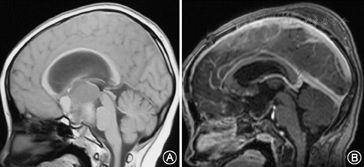

根据术者术中判断及术后影像学判定肿瘤切除程度(图1,图2)。本组病例肿瘤全切除124例(73.4%),次全切32例(18.9%),大部分切除13例(7.7%)。169例患者临床资料见表1。本组无手术相关死亡病例,术后住院8~85 d,平均17.3 d。垂体柄完整保留104例,部分保留21例,垂体柄与肿瘤一起切除21例,术中未见垂体柄23例。5例选择前纵裂入路术中切断前交通动脉,术后无不良反应。6例巨大颅咽管(最大径>6 cm)在术中磁共振辅助下手术,其中4例全切除,2例次全切除。

所有患者术前均行头颅MRI平扫及加强扫描,126例行CT检查。头颅CT有明确钙化的73例。肿瘤大多数位于鞍上,中线生长,压迫视神经及视交叉,向上生长进入三脑室内,部分肿瘤可突入脚间池内,少部分肿瘤向侧方生长甚至突入侧脑室内。室间孔或中脑导水管阻塞者可出现幕上脑室扩大,合并中度至重度脑积水患者28例。肿瘤最大径1.5~7.8 cm。囊性23例,囊实性125例,实质性21例。增强扫描肿瘤囊壁和实质性部分有明显强化。肿瘤主体位于鞍内17例,主体位于鞍上未侵及三脑室的51例,主体位于鞍上侵及三脑室内外的95例,其中进入侧脑室的5例。完全在第三脑室内6例。